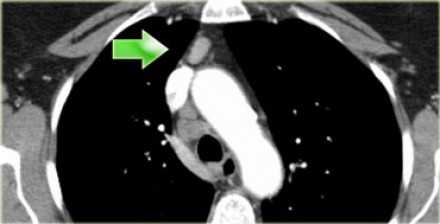

На изображении слева 3А узел в преваскулярном пространстве. Обратите внимание так же на ниже расположенные паратрахеальные узлы справа относящиеся к 4R группе.

4R. Правые нижние паратрахеальные лимфатические узлы

- Верхняя граница: пересечение нижнего края левой плечеголовной вены с трахеей.

- Нижняя граница: нижний края непарной вены. 4R узлы распространяются до левого края трахеи.

На изображении слева мы видим 4R паратрахеальные узлы. Кроме того здесь представлен узел кнаружи от дуги аорты, то есть 6 группы.